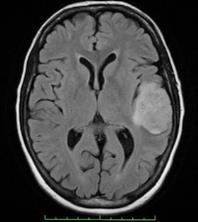

The MRI dataset utilized in our study encompasses approximately2100images,representingbothnormaland abnormal brain scans. To enhance the quality of these images,weemployatechniqueknownassigmafilteringto reducenoiseinterference.

This process involves analyzing the pixels within a designatedareaandsmoothingoutvariationsthatexceeda

certain threshold. By applying sigma filtering, we aim to improve the clarity and accuracy of the images, thus facilitatingmoreprecisetumordetection.

After processing the images, the subsequent step is segmented.Hither,segmentationisbeingdoneemploying thresholding.Theunderlyingconceptofthresholdingisto simplify the visual data analysis. Thresholding bethinks a vastly popular segmentation technique utilized to differentiate the object pondered as a forefront from its surrounding. In this scenario, we are utlilizing binary thresholdingforsegmentation.Inbinarythresholding,each pixel enduresthesamethresholdvalue.Supposethepixel intensityvalueislesserthanthethreshold,itgetssetto0 (black);ifnot,itgetssetto255(white).

Segmentationstandsastheprocessofcarvinganimageinto myriad segments and isolating the tumor from regular tissues. Segmentation method owns the capacity to recognizeordeterminetheaberrantportionfromtheimage, cateringtotheanalysisofsize,volume,location,texture,and shapeofextractedimage.